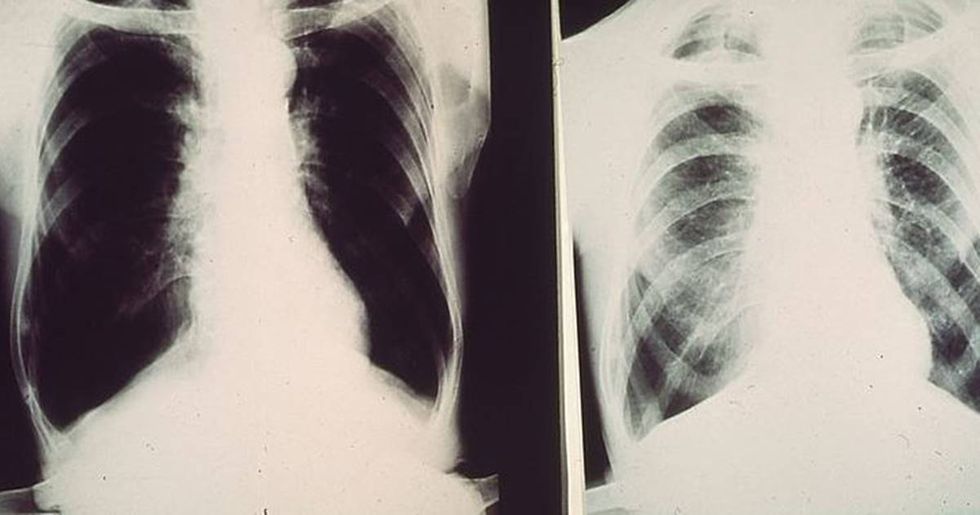

Black lung disease is scarring of the lungs caused by inhaling coal dust over a long period of time. According to WebMD, 16 percent of coal miners may eventually develop health issues in their lungs from inhaling coal dust.